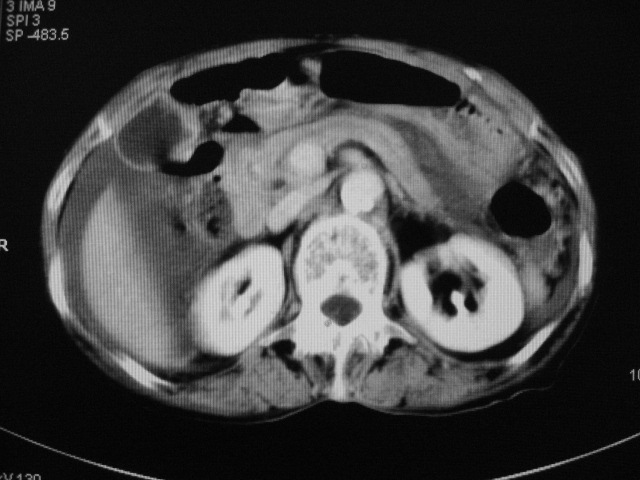

以下是引用zjzjr在2007-9-20 19:15:00的发言:[br]慢性胆囊炎伴炎性息肉可能性大.腹水.

以下是引用默契在2007-9-20 17:29:00的发言:[br][br] [br] 考虑:1、胆囊占位性病变(以癌可能性大);[br] 2、中量腹水。 [br] [br]

以下是引用快乐男生在2007-9-20 15:32:00的发言:[br]图像质量不好:[br]胆囊增大,囊壁增厚,[br]可见结节突出囊腔内,[br]增强后与囊壁相仿.[br]考虑多为胆囊慢性炎症伴有胆囊体部的息肉